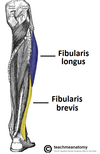

What is this muscle

The levator scapulae